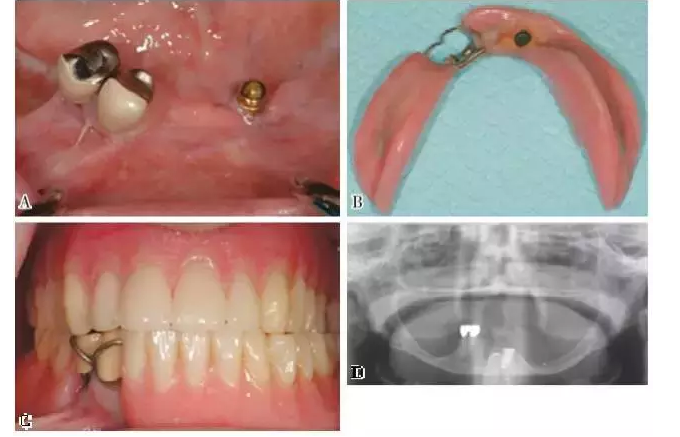

圖3~6展示了相關(guān)臨床病例。

圖4:KennedyⅡ類(lèi)缺損??缭较骂M中線(xiàn)的較長(zhǎng)亞類(lèi)缺失間隙。種植體提供了支持力和固位力,改善了義齒的舒適和功能,同時(shí)減少了下頜中切牙上的功能性應(yīng)力